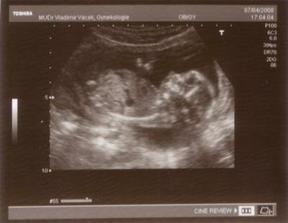

7.4.UTZ na trippl testy dopadl dobře a podle všeho čekáme CHLAPEČKA